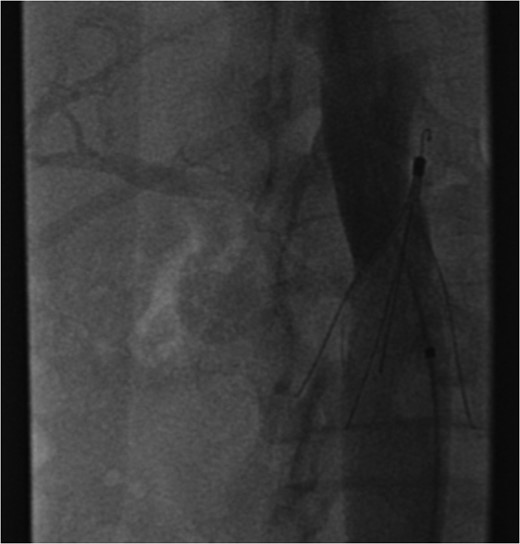

Excessive tilting of the IVC filter causes the hook of the filter to appear outside of the lumen of the IVC.

The patient's coagulopathy was treated and she underwent a laparotomy and evacuation of a large duodenal haematoma. After division of adhesions, a tense duodenal wall was revealed with splitting of the serosal layer. A large haematoma, of about 500 mls volume, was removed from the subserosal layer without breach of the muscularis. The penetrating strut of the IVC filter was able to be palpated within the duodenal wall but was not on view after haematoma removal. There was considerable inflammation of the retroperitoneum as well as scarring from the previous arterial bypass surgery. There was no contamination of the peritoneum with bowel contents. It was thought preferable to remove the IVC filter via the transvenous route rather than expose the IVC and risk large blood loss and arterial graft contamination in the event of duodenotomy.